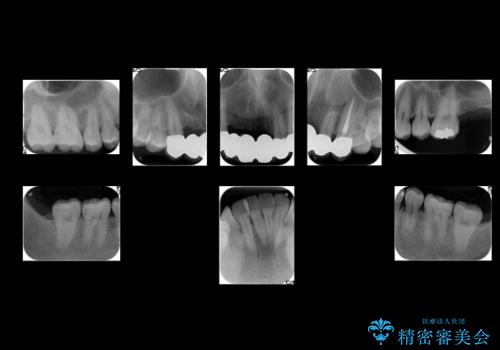

- 前歯のブリッジのやりかえおよび銀の詰め物をセラミックにしたいと来院。

過去に事故で前歯を折って、ブリッジにしたとのことでしたが、支台となる歯が持たない状況で、ブリッジを延長せざるを得ない状況でした。

長いブリッジへ設計変更になるため、下の前歯のがたつきが気になるのであれば、先に矯正治療をしてから最終的なブリッジを入れることをご提案し、全て行なっていくことになりました。

上の前歯の本数が少ないことから、小臼歯を4本抜歯するのではなく下の前歯を1本だけ減らして並べました。

左上1番は再根管治療を行いましたが途中で破折が確認されたため、抜歯しています。

また、大臼歯の銀歯もセラミックに全てやりかえています。

左上7番は歯周病によりやむなく抜歯となり、インプラントをおすすめしましたが、希望されませんでした。